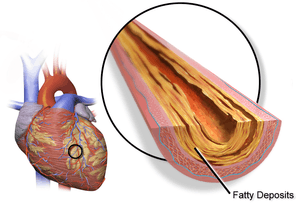

| Illustration depicting atherosclerosis in a coronary artery. | |

Typically, coronary artery disease occurs when part of the smooth, elastic lining inside a coronary artery (the arteries that supply blood to the heart muscle) develops atherosclerosis. With atherosclerosis, the artery's lining becomes hardened, stiffened, and swollen with calcium deposits, fatty deposits, and abnormal inflammatory cells - to form a plaque. Deposits of calcium phosphates (hydroxyapatites) in the muscular layer of the blood vessels appear to play not only a significant role in stiffening arteries but also for the induction of an early phase of coronary arteriosclerosis. This can be seen in a so-called metastatic mechanism of calciphylaxis as it occurs in chronic kidney disease and haemodialysis (Rainer Liedtke 2008). Although these patients suffer from a kidney dysfunction, almost fifty percent of them die due to coronary artery disease. Plaques can be thought of as large "pimples" that protrude into the channel of an artery, causing a partial obstruction to blood flow. Patients with coronary artery disease might have just one or two plaques, or might have dozens distributed throughout their coronary arteries. A more severe form is chronic total occlusion (CTO) when a coronary artery is completely obstructed for more than 3 months.[46]